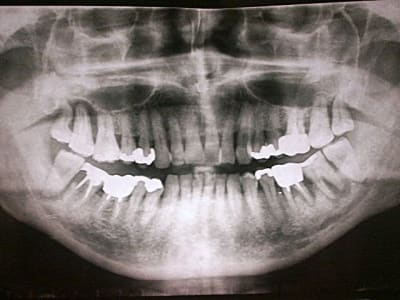

patient, 65 ans, ami proche de la famille, pére d'un très bon ami d'enfance.

douleurs récurrentes au maxillaire droit à la mastication.

sensations de dents + ou - mobiles au max D et mand G.

Habitudes: visite annuelle chez son CD. a effectué les soins et prothèses conseillés. Pas de gros travaux entrepris depuis 20 ans. utilise un hydropulseur en plus du brossage (mais ne sait surement pas que son efficacité sur la PD est nulle).

Dernière visite chez son CD: 3 mois... pour la même raison. RAS tout va bien (???) + un ATB et roule ma poule... (???).

n'a plus trop confiance dans son CD...

motivation: ok. prêt à faire des kms pour venir me voir. prêt à faire de gros rdv (2H).

Je l'ai envoyé faire une pano en attendant de le voir en consultation. Bigre!!!!

premières impressions?

Manifestement alvéolyse horizontale généralisée, 25% de perte d'attache à 65 ans : je penche pour une parodontite chronique de l'adulte.

Je soupçonne aussi un trauma occlusal.

Déjà on commencera par la base: Bilan général + dentaire + retroalvéolaires au moins sur toutes les postérieures + OHM + modéles d'étude pour analyse occlusale.

Cas typique (enfin je crois) où il est urgent de ne pas extraire, ni de se jeter sur le bistouri si on se met dans un "esprit paro" et que la compliance du patient est ok, sauf 18 (dent courte + carie M) et 17??? mais risque de déporter toutes les forces de mastication à G et c'est la 37 qui va devenir douloureuse.

il a tout usé a plat? avc juste le pano, j'ai un peu de mal à juger de l'occlusion en dynamique. Il peut se mettre ne pr ou en lateralité juste sur les molaires qui ont le plus dérouillé? IL bruxe? ou plus exactement, il " Clinche" ?

ce cas présenté par tonio est un classique .....parodontite de l'adulte surement plus facteur occlusal ( cette patiente est en béance incisvo canine surement )